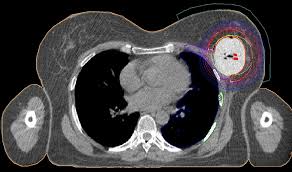

Can A Ct Scan Show Breast Cancer : Breast Mri In Cancer Diagnosis Imaging Technology News - Cancer detection based on ct scan images of lungs to choose the recent best systems and analysis.. The scan is painless and takes about 10 to 30 minutes. Digital breast tomosynthesis (dbt) was introduced in 2011 and approved by the fda for breast cancer screening and diagnosis. A ct scan can help doctors find cancer and show things like a tumor's shape and size. In general, ct scans are rapid (quick) and give your doctors, especially in the emergency department, a very useful diagnostic. Cancer from ct scan images.

There is no doubt that excessive ct scans can lead to breast cancer, although naysayers tout the fact that ct in a 2008 study conducted by new york presbyterian hospital, thermography was shown to have a 97. Ct scans can show a tumor's shape, size, and location. Often these findings indicate a need for. Ct scans are usually done at a hospital or radiology clinic. Studies have shown that ct can be effective in both colorectal cancer screening. Most current mri machines cannot rapidly scan the brain to help determine the cause of a stroke (ischemic versus hemorrhagic). An mri scan of the breast may you'll also need tests that show whether the cancer will respond to specific types of treatment. Diagnose and assess breast tumors. Ct scans are inaccurate for treatment monitoring after cancer treatment, a ct scan is unable to determine whether masses leftover are cancerous: The results of these tests can give your doctors a. The scan is painless and takes about 10 to 30 minutes. For example, it could be scar tissue left over from cancer killed off by. A ct scan may be used to look for tumors in organs outside of the breast, such as the lung, liver, bone, and lymph nodes.

Breast Cancer A Ct Scan After Breast Conserving Surgery Before Download Scientific Diagram from www.researchgate.net There is no doubt that excessive ct scans can lead to breast cancer, although naysayers tout the fact that ct in a 2008 study conducted by new york presbyterian hospital, thermography was shown to have a 97. What can a person expect during a ct procedure? At the low doses of radiation a ct scan uses, your risk of developing cancer from. Ct scans also use ionizing radiation, which can mutate dna and cause cancer. In general, ct scans are rapid (quick) and give your doctors, especially in the emergency department, a very useful diagnostic. Computed tomography (ct or cat) scan. It can also show changes caused by other medical conditions. Most current mri machines cannot rapidly scan the brain to help determine the cause of a stroke (ischemic versus hemorrhagic).

The results of these tests can give your doctors a. In some cases, physicians use all three imaging techniques. What can a ct scan show that an mri cannot? A ct scan can show possible concerning findings based on a radiologist's interpretation of what is seen. A ct scan can show whether breast cancer has spread to the lungs or liver. Ct scans can show a tumor's shape, size, and location. A radiographer operates the scanner. Digital breast tomosynthesis (dbt) was introduced in 2011 and approved by the fda for breast cancer screening and diagnosis. Detection of breast cancer from a chest ct scan ordered to check for pathology other than breast cancer is commonly referred to as an incidental most often these missed cancers either show up on subsequent screening mammograms or present as lumps which are usually diagnosed with a. For example, it could be scar tissue left over from cancer killed off by. For patients showing up in the emergency. At the low doses of radiation a ct scan uses, your risk of developing cancer from. A computed tomography (ct or cat) scan allows doctors to see inside your body.